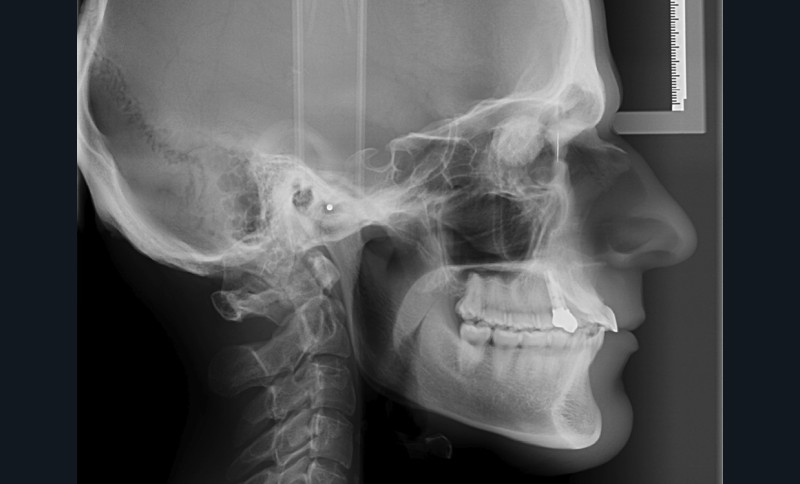

Après examen clinique, des photographies, des moulages, un panoramique et une téléradiographie de profil sont réalisés (fig. 1). Le traitement n’est pas simple mais le patient est motivé.